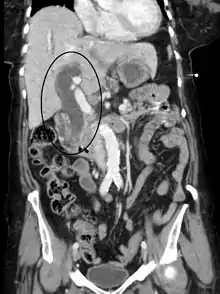

Imaging

Medical imaging such as ultrasound, CT scan, and HIDA scan are useful for detecting bile-duct blockage.[40]